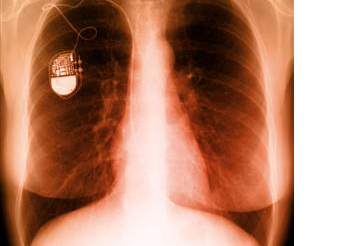

The pacemaker helps the arrythmias of the human heart. The arrythmias is a problem with the rythme and the rate of the heartbeat. The sensors called electrodes are in the pacemaker which helps monitor and control your heartbeat. The electrodes feel your hearts activity and send data through the wires and back to the computer. If your heart has not got a good rhythm the computer directs the generator to send electrical pulses through the wires and into the heart.

Here's a light hearted look at pacemakers.